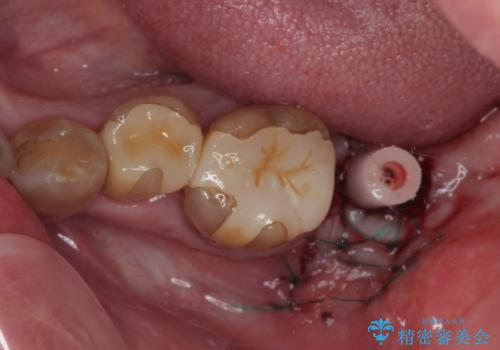

左下はインプラントによる補綴治療を行いました。

- 外科手術のため、術後に痛みや腫れ、違和感を伴います

- メンテナンスを怠ったり喫煙により、お口の中に大きな悪影響を及ぼすインプラント周囲炎等にかかる可能性があります